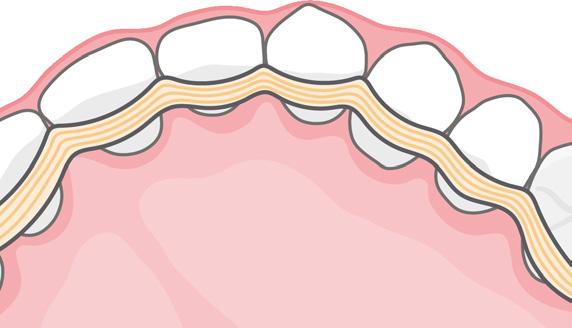

FIG. 2: Encuentre información sobre estos tratamientos regenerativos preventivos en «The New Daily Practice»: regeneración periodontal, relleno del gap, preservación de la cresta y regeneración preventiva del tejido blando.

es una capa densa de tejido conectivo vascular que cubre la superficie de la mayoría de nuestros huesos. Sirve como protección y como canal para el suministro de la sangre y los nutrientes, y proporciona células progenitoras para la regeneración de los tejidos.

Una vez dañado durante la ROG, el periostio tarda entre 4-6 semanas en repararse.2-3